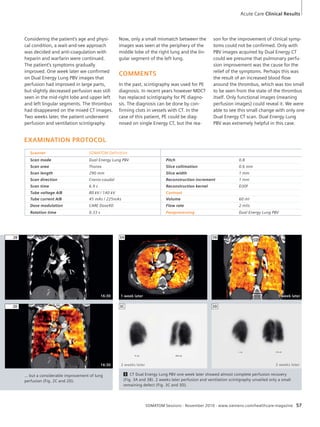

48 Total Occlusion of the Left Superior

Pulmonary Vein by a Metastasis

Detected with Dual Energy CT